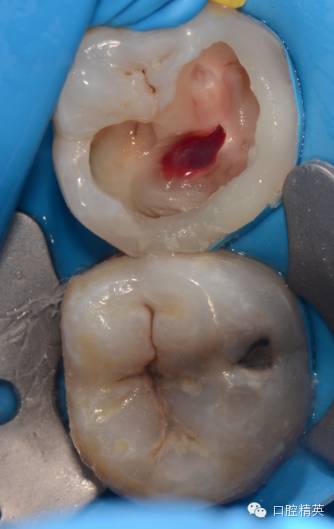

病例1:

病例是36一次性根充,患者女性,68岁,半年前因冷热不适36外院有充填史,但无好转,近日加重,夜间痛自发痛,疼痛放散至头面部,查:36冷测(++)扣痛阳性,不松,牙髓电活力测试17,龈正常,诊断:不可逆性牙髓炎

处:36碧蓝阻滞麻醉,上橡皮障

这是个严重钙化的牙齿

严重钙化,打开根本找不到根管口![今天的病例,36一次性根充]()

超声去除钙化物,测量根管长度,逐级预备到9号先锋锉,并配合大量次氯酸钠和edta冲洗,冲洗后髓底非常干净清楚,特别利于你找到根管